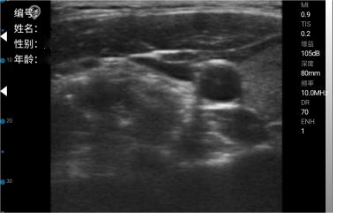

Common parameter adjustment for B mode

Gain

The degree of increase in the intensity of ultrasonic echo signal is visually represented as the brightness of the image on the ultrasound image.

Increasing the gain makes the image brighter, presenting more information, but also increasing the noise;

decreasing the gain makes the image darker, presenting insufficient information, but suppressing the noise.